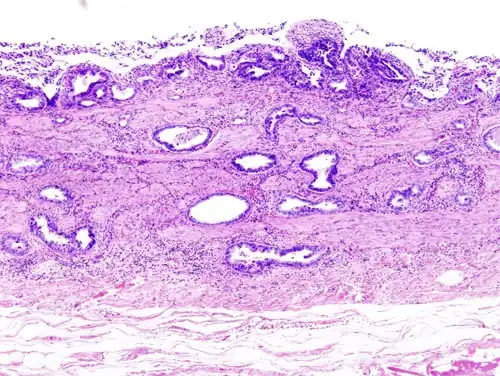

Incidentally discovered gallbladder cancer (adenocarcinoma) following a cholecystectomy. -